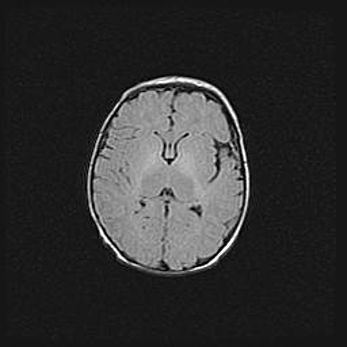

Сообщающаяся гидроцефалия. Кистозная энцефаломаляция головного мозга.

Возраст: 3 месяца 4 дня

Вес: 3100 г

Пол: женский

Окружность головы: 34 см

Срок гестации: 31 неделя

Кистозная энцефаломаляция головного мозга - одна из форм поражения головного мозга в детском возрасте. Характеризуется возникновением множественных и распространённых кист в коре, белом веществе и подкорковых образованиях головного мозга у плодов, новорождённых и детей раннего возраста. Развитие кистозной энцефаломаляции связано с внутриутробной асфиксией и гипотонией, родовой травмой, тромбозом синусов, пороками развития сосудов, инфекциями, сепсисом и другими причинами. Наиболее значимые инфекционные агенты: вирусы простого герпеса, цитомегалии, краснухи, токсоплазмы, энтеробактерии, золотистый стафилококк и другие.